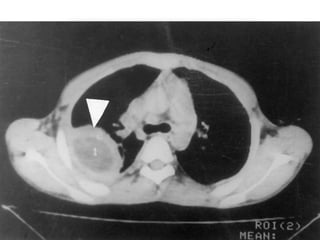

KH à localisation hépatique et   KHP fissuré aspect serpigineux de

pulmonaire                       la membrane proligère

a.4. Echographie thoracique

• Elle est utile dans les kystes superficiels.

• Confirme la nature liquidienne de l’opacité Rx